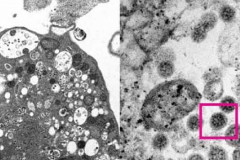

Ծխողներն ավելի շատ են ենթակա COVID-19-ի ծանր ընթացքի վտանգին. հետազոտություն Եկեղեցականների նոր նշանակումներ են կատարվել ԱՀԿ-ն խորհուրդ է տվել չսահմանափակել միջազգային ուղևորությունները և այլ միջոցներ ... Հայաստանում հաստատվել է կորոնավիրուսով վարակվելու 621, մահվան՝ 1 նոր դեպք Որոշման տրամաբանության հետ կապված որևէ խնդիր չկա, բայց վերահսկողության հետ կապվա... Լարսի ճանապարհը փակվել է բեռնատարների համար Հայաստանի ճանապարհներին մերկասառույց ու բուք է. մի շարք բնակավայրերում ձյուն է տ... Լույս չի լինելու Երկրի կողքով պոտենցիալ վտանգավոր աստերոիդ է անցել Պատերազմի հետևանքով զոհերի թիվը կազմում է 3809 անձ, 199 զինծառայողի և 21 քաղաքաց... Հանրապետության որոշ ճանապարհներին բուք է Կոկորդի ցավ, քթից արտահոսք, չոր հազ, գոտկատեղի ցավ. «Օմիկրոն» շտամի ախտանշանները Սպասվում է ձյուն. եղանակը՝ առաջիկա օրերին COVID-19-ով հիվանդացության գլոբալ աճն անցած շաբաթ կազմել է 20 տոկոս. ԱՀԿ Մասիսում բախվել են Mitsubishi Colt-ն ու 06-ը. 6 վիրավորներից 2-ը երեխաներ են COVID-19-ը տարածների մոտ ուղեղի վնասվածքի հետքեր են հայտնաբերվել «Օմիկրոնից» պաշտպանության համար արդյունավետ է COVID-19-ի դեմ պատվաստանյութի բուս... Ավիահաղորդակցությունը Թուրքիայի և Հայաստանի միջև կսկսվի փետրվարի 2-ից Երևանում 24-ամյա վարորդը Opel-ով գլխիվայր շրջվել է. կա վիրավոր Հայաստանում հաստատվել է կորոնավիրուսով վարակվելու 563, մահվան՝ 3 նոր դեպք «Օմիկրոնից» հետո կորոնավիրուսի նոր մանրէահիմքեր կհայտնվեն. ԱՀԿ ղեկավար 6 ժամ լույս չի լինի ՀՀ մի շարք տարածաշրջաններում ձյուն է տեղում Դելտակրոն. Ինչ է հայտնի Կիպրոսում հայտնաբերված կորոնավիրուսային շտամի մասին Փակ և դժվարանցանելի ավտոճանապարհներ կան․ ԱԻՆ Դիվանագետները նվերներ են հանձնել իրենց հայաստանցի երիտասարդ հայրենակիցներին Վթարի հետևանքով դադարեցվել է նշված հասցեների գազամատակարարումը Նշված հասցեներում հոսանքազրկումներ կլինեն Հայաստանում կտեղադրվի Քրիստոսի աշխարհի ամենաբարձր արձանը Մեկ օրում բացահայտվել է 72 հանցագործություն. հայտնաբերվել է 5 հետախուզվող